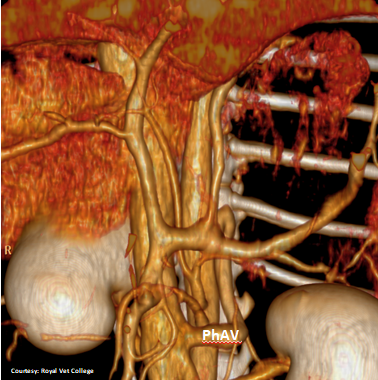

(Phrenic vein entrance)

Does the RIGHT GASTRIC VEIN (RGV) contribute blood to the shunt?